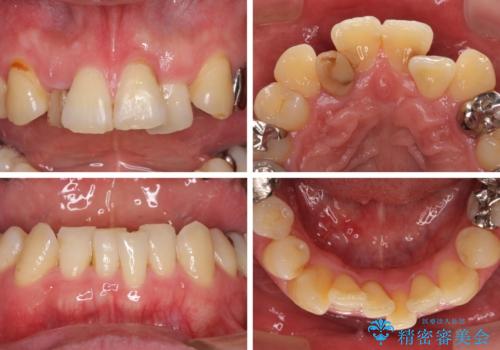

- 奥歯の痛みと前歯のデコボコを気にして来院された患者様です。

左右下顎の大臼歯は、ともに歯根が破折しており、抜歯が必要な状態でした。

咬み合わせは受け口傾向であり、上顎前歯の叢生が顕著であったことから、第1小臼歯抜歯による矯正治療も検討しましたが、下顎大臼歯を左右ともに抜歯するため、非抜歯による矯正治療を行うこととしました。

矯正治療でインプラント埋入を行い、矯正治療後に気になる前歯と合わせてオールセラミッククラウンによる補綴治療を行うこととしました。